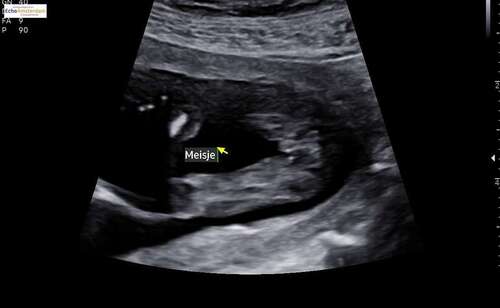

Ja ! Zeker een meisje

Haha dank je! ik heb aan de echoscopiste gevraagd of ze het wel eens fout had gehad 😅 maar ik had de echo gepland na 16 weken om wat meer zeker te zijn.. dus fijn dat het zo duidelijk is 🥰

@Peterpan, in het vorige deel gaf je aan, (zowel nub als pottyshot) dat ons kindje een meisje is. Je had gelijk! :) echo gehad met 15 weken en 3 dgn. Het is een meisje volgens de echoscopist!